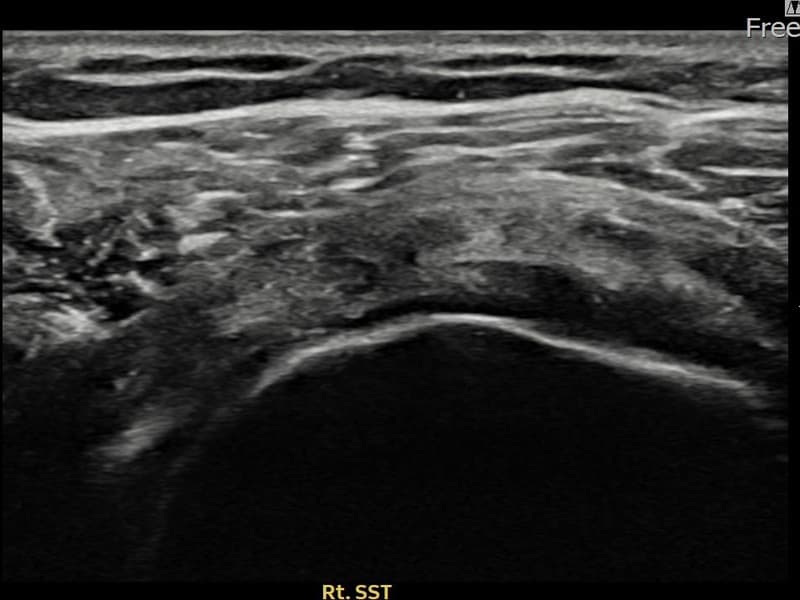

After

시술 전 초음파 측정 결과 파열 크기는 12mm × 7mm (힘줄 두께의 약 55% 결손)로 확인되었습니다. 시술 전 초음파에서 우측 극상근건의 광범위한 에코 단절과 힘줄 내 복합 소견이 확인되었습니다. 시술 후 초음파에서 파열 부위에 재생 조직이 형성되며 힘줄 연속성이 회복된 것이 관찰되었습니다.

50대 중반 남성 환자분으로, 우측 어깨 통증이 오래되어 파열이 상당히 진행된 상태였습니다. 다방향에서 초음파 평가를 시행한 결과 관절면측 파열이 넓게 퍼진 진행형 소견이 확인되었습니다. 파열 범위가 넓어 일반 보존 치료로는 한계가 있다고 판단하여 초음파 유도 하 축소봉합술을 시행하였습니다. 시술 후 충분한 보조기 착용 기간을 유지하고 단계적 재활을 진행하였으며, 14주 후 추적 초음파에서 파열 부위의 구조적 안정화가 확인되었습니다.